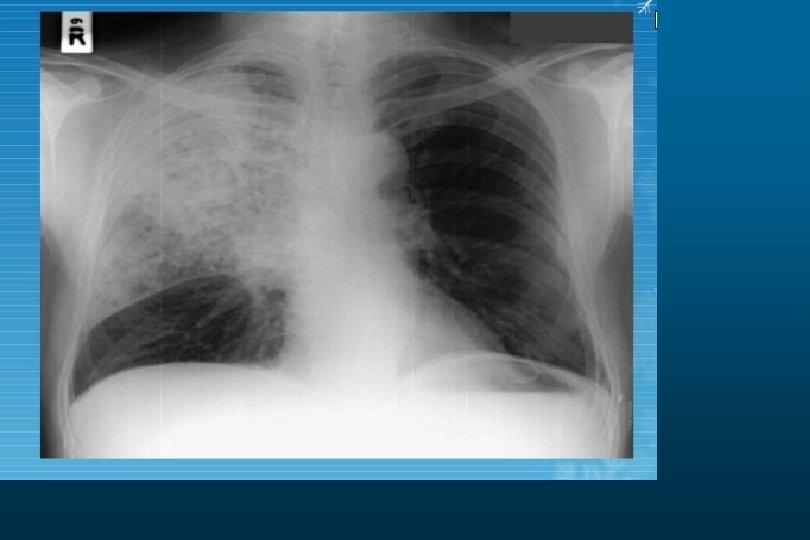

Pleural Effusion